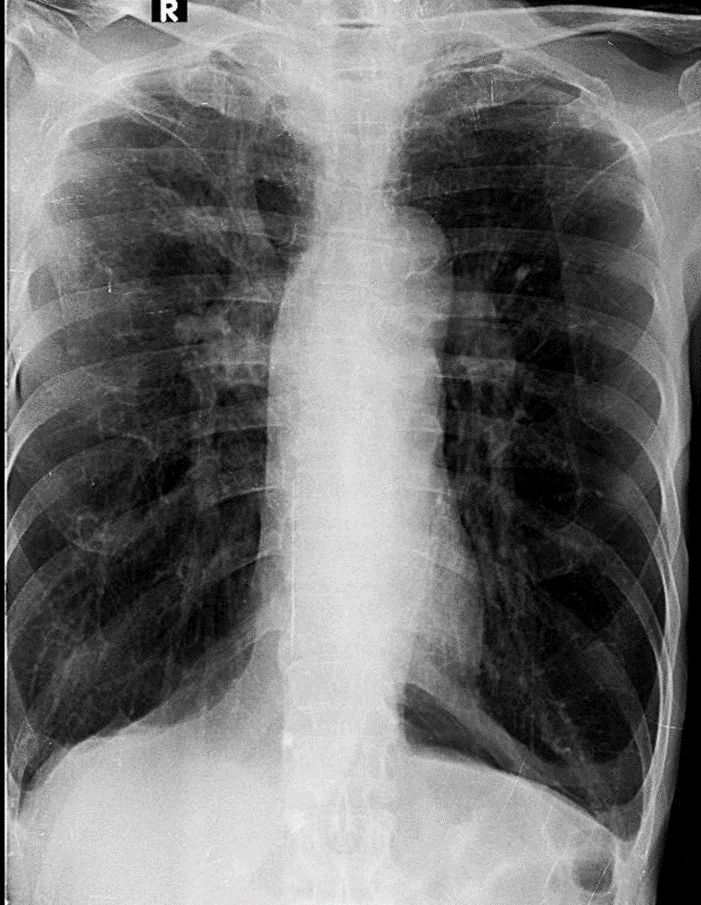

Hãy phân tích tình huống

1-Xơ + khí phế thũng rải rác hai phổi 2-Bóng tim nhỏ